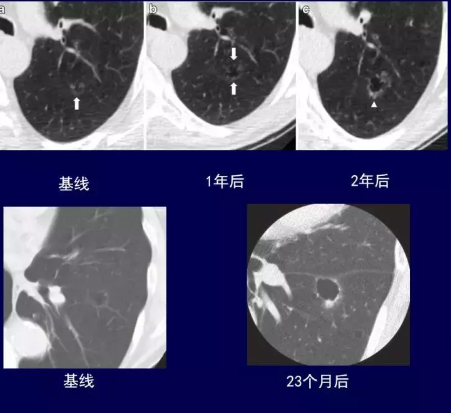

这是一个囊腔型肺癌的随访变化过程

不仔细看非常容易误诊为肺大泡,如果当做肺大泡来处理,临床结局就非常不一样了。

这个病人的最后病理是浸润性腺癌。

临床工作中从形态学上把这种肺癌叫做囊腔型肺癌。

囊腔型肺癌的囊腔一般壁比较厚的,且不均匀,生长缓慢,随访过程中空腔可增大、缩小或不变。

如果仔细观察,能早期发现,手术的效果是非常好的。